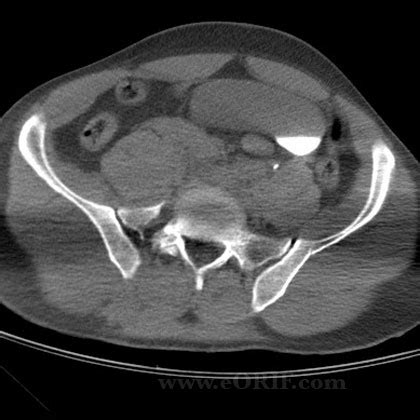

The majority of those injuries are suffered. Children with open triradiate cartilage have different fracture patterns than do children whose triradiate cartilage has (obq10.144) of all the pelvic ring injury types, anteroposterior compression type iii pelvic ring injuries have the highest rate of which of the following? The majority of those injuries are suffered. Current concepts review souborný referát. Early urinary complications of fractures of the pelvis. We hope this list makes getting to coding. As per american congress of obstetricians and gynecologists' guidelines, a well women exam includes both a pelvic exam as well as a clinical breast examination. Any associated fracture of pelvic ring ; What types of pelvic fracture are there? › icd 10 code for pelvic fracture aftercare. Clinical orthopaedics and related research. Pelvic ring injuries in children. Encounter for other specified special examinations. Icd 10 pelvic fracture unspecifiedall software. S32 fracture of lumbar spine and pelvis. A review publication of the radiological society of north america, inc. Therefore, fractures of the pelvis occur most commonly.